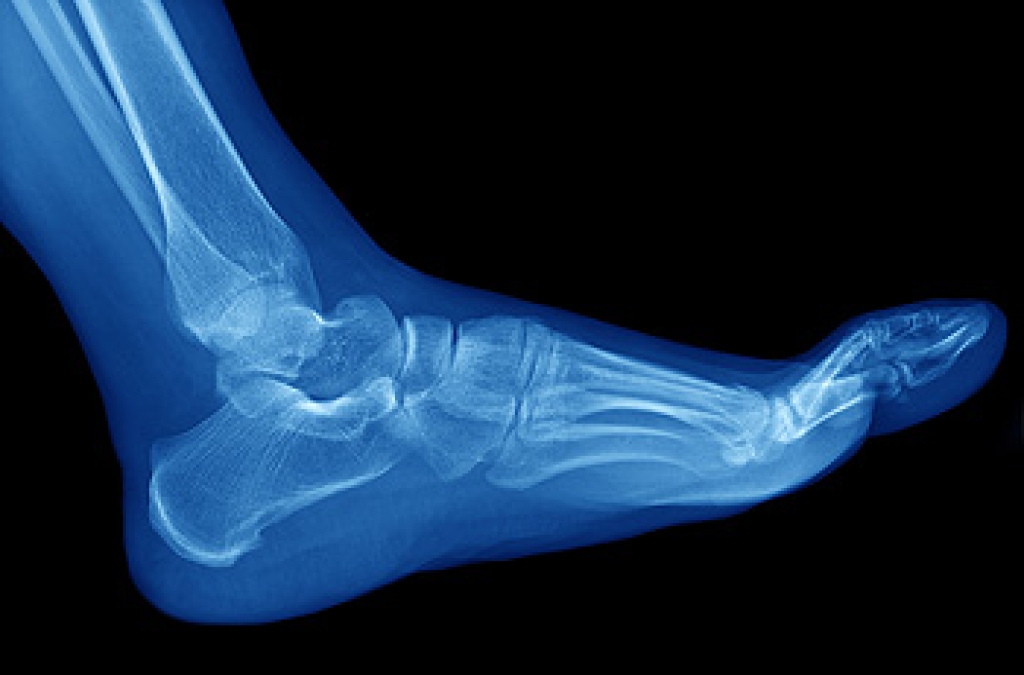

Neuropathy can generally be referred to as a disease or dysfunction of the nerves. There are different forms of neuropathy which can occur in various locations of the body. When neuropathy affects the feet, it is a malfunction within the peripheral nervous system—which is a network of nerves outside of the central nervous system (comprising the spinal cord and brain) which controls the feet, hands, legs, and arms. This type of neuropathy is referred to as peripheral neuropathy. Neuropathy can be caused by diabetes, autoimmune diseases, infections, alcoholism, genetic disorders, toxins, medications, tumors, and more. Sometimes there is no known cause for neuropathy. Peripheral neuropathy can cause numbness, tingling, pain, or extreme sensitivity to touch in the feet. It may even cause a loss of feeling in the feet which may lead to an inability to detect rapidly developing sores. If you have any of these symptoms, see a podiatrist as soon as possible to devise an appropriate treatment plan.

Neuropathy is a condition that leads to damage to the nerves in the body. Peripheral neuropathy, or neuropathy that affects your peripheral nervous system, usually occurs in the feet. Neuropathy can be triggered by a number of different causes. Such causes include diabetes, infections, cancers, disorders, and toxic substances.